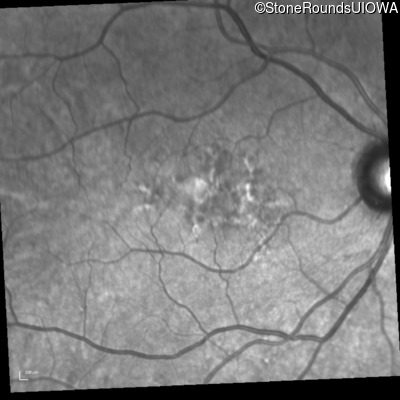

Infrared Fundus Photograph - Right - 20/25 +2

Exemplar

Infrared Fundus Photograph - Left - 20/50 -1

Infrared Fundus Photograph - Right - 20/20 +1

Infrared Fundus Photograph - Left - 20/63 -1

Infrared Fundus Photograph - Right - 20/20 -2

Infrared Fundus Photograph - Left - 20/50

Infrared Fundus Photograph - Right - 20/20 +2

Infrared Fundus Photograph - Left - 20/40 -2

Infrared Fundus Photograph - Right - 20/20

Infrared Fundus Photograph - Left - 20/63